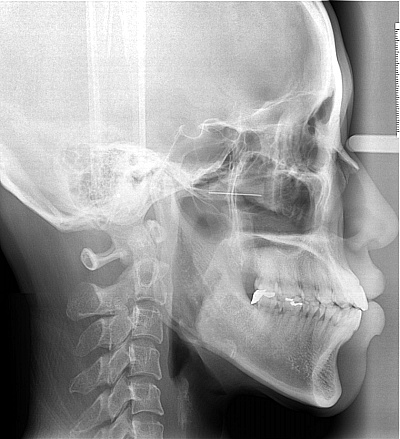

교정 중 무턱가능여부

작년 7월말 교정을 했으므로 이제 만 7개월이 넘었습니다. 비발치로 진행중이구요, 일전에 치아가 앞으로 튀어나는 것으로 문의를 드린적이 있었습니다. 지난달 월치료시 이 문제에 대하여 상의를 드리자 발치를 해야...

돌출 개선될 수 있을까요

철사맨 선생님 안녕하세요~^^ 전부터 돌출된 입이 컴플렉스 였어요. 나이 드니까 더 두드러지는것 같아 속상하고 주위에서도 입을 가려야 이쁘다고 하고 ㅠㅠ 30대 초반인데 그동안 생각만 하고 있던 교정을 더 늦기...

무턱개선된다고햇는데 비교해주세여 해도되나여

거의 2년 7개월전에 교정시작했습니다.. 교정 다하면 무턱이 개선이된다고하셧는데여 제가 요즘 안물어봣는데 담에 월치료할때 물어봐서 저 개선된거에요 말해도되나요 아직두 앞니가 안들어갓는데여 치아를 좀깍는다...